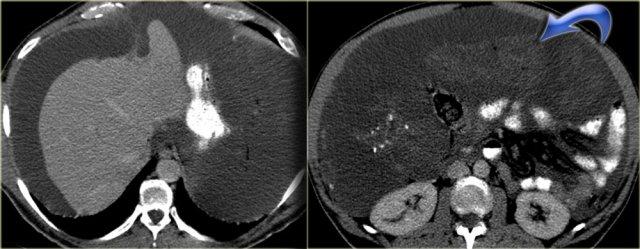

Hình bên trái là bệnh nhân nam 33 tuổi than phiền về tình trạng bụng ngày càng to, cảm giác đầy bụng và sờ thấy khối ở bụng.

Trước hết, đây là tổn thương có bờ rõ với giảm tỷ trọng trên CT.

Có ngấm thuốc nhẹ xung quanh tổn thương và một số dải ngấm thuốc nhỏ bên trong tổn thương.

Trên MRI, tổn thương giảm tín hiệu trên chuỗi xung T1W như dự kiến.

Trên chuỗi xung T2W, tổn thương tăng tín hiệu tương đối.

Kết hợp với giảm tỷ trọng trên CT, điều này cho thấy có chứa mucin bên trong tổn thương.

Đặc điểm này rất gợi ý chẩn đoán u xơ mạc treo.

Mức độ ngấm thuốc trên MRI rõ hơn so với trên CT.

Trên CT, giảm tỷ trọng của mucin nổi bật hơn, nhưng trên MRI chúng ta có thể đánh giá sự ngấm thuốc tốt hơn.

Điều này cho thấy tổn thương được tưới máu tốt.

Hình bên trái là bệnh nhân khác mắc u xơ mạc treo.

Lưu ý tổn thương này không có tỷ trọng thấp.

Tổn thương này có mô đệm dạng collagen hoặc xơ hóa nhiều hơn.

Vì vậy có hai thể hình ảnh khác biệt.

Hình bên trái là một trường hợp điển hình hơn với khối u giảm tỷ trọng nằm ở mạc nối lớn (hình trên) và dây chằng vị-lách (hình dưới).